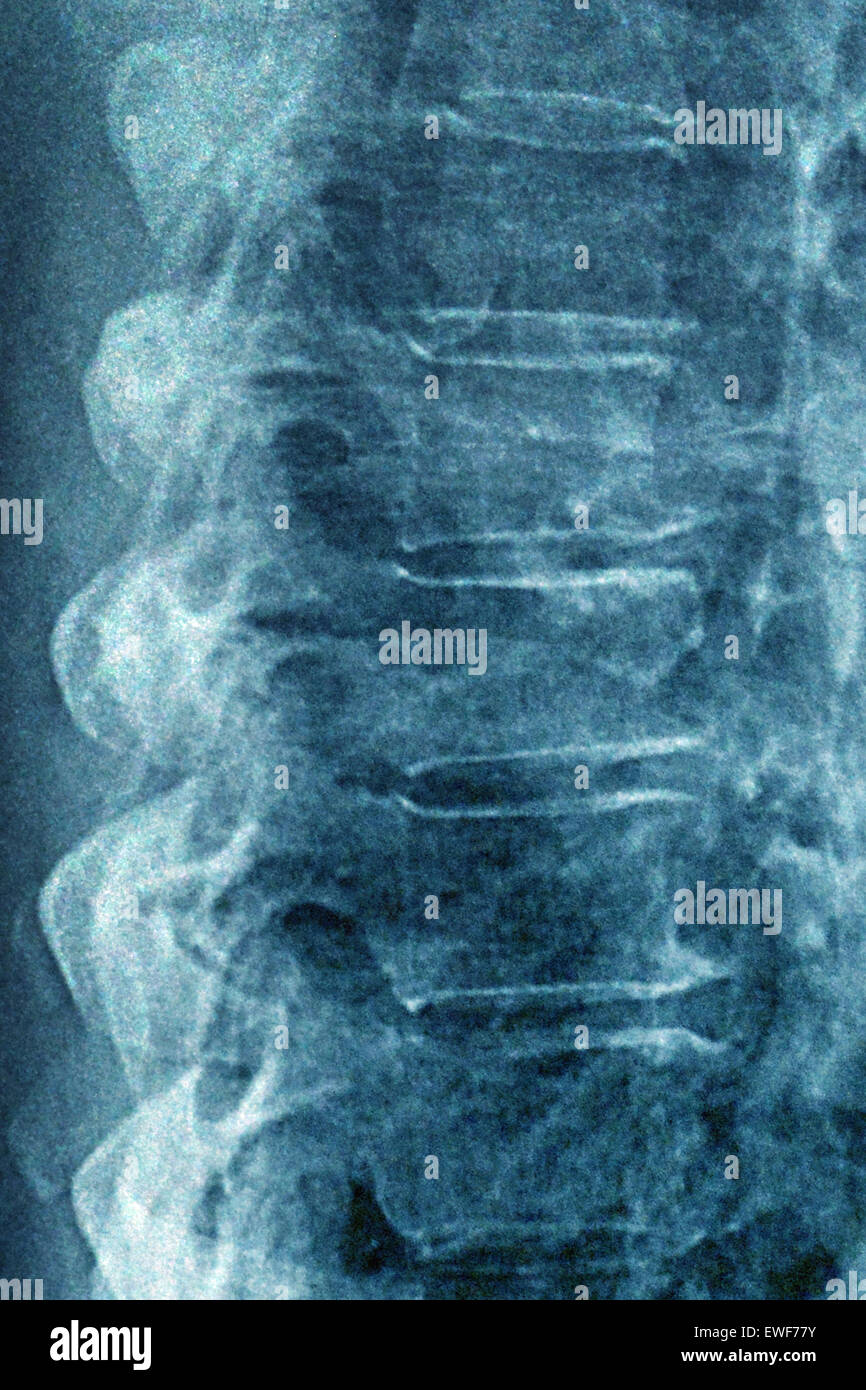

From www.alamy.com

Osteoarthritis. Xray of the thorarcic spine of a 64 year old man with Vertebral Disc Osteoarthritis Osteoarthritis of the lumbar region of the spine is characterized by morning stiffness (for about 30 minutes) and usually involves more than one vertebra. In a young and healthy back, rubbery discs between the. It is also known as facet joint arthritis, facet joint. Arthritis in the low back has similar symptoms and can cause pain in the back and.. Vertebral Disc Osteoarthritis.